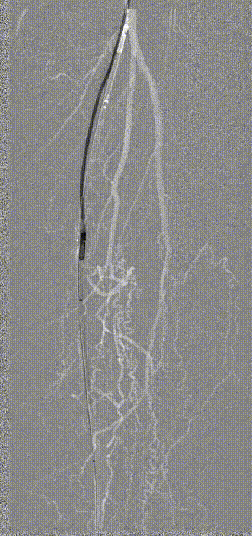

图为:2023年11月 2年后复查

2年后(2023-11)复查

下肢动脉CTA提示左股腘动脉通畅,DES区域未见内膜增生管腔丢失表现